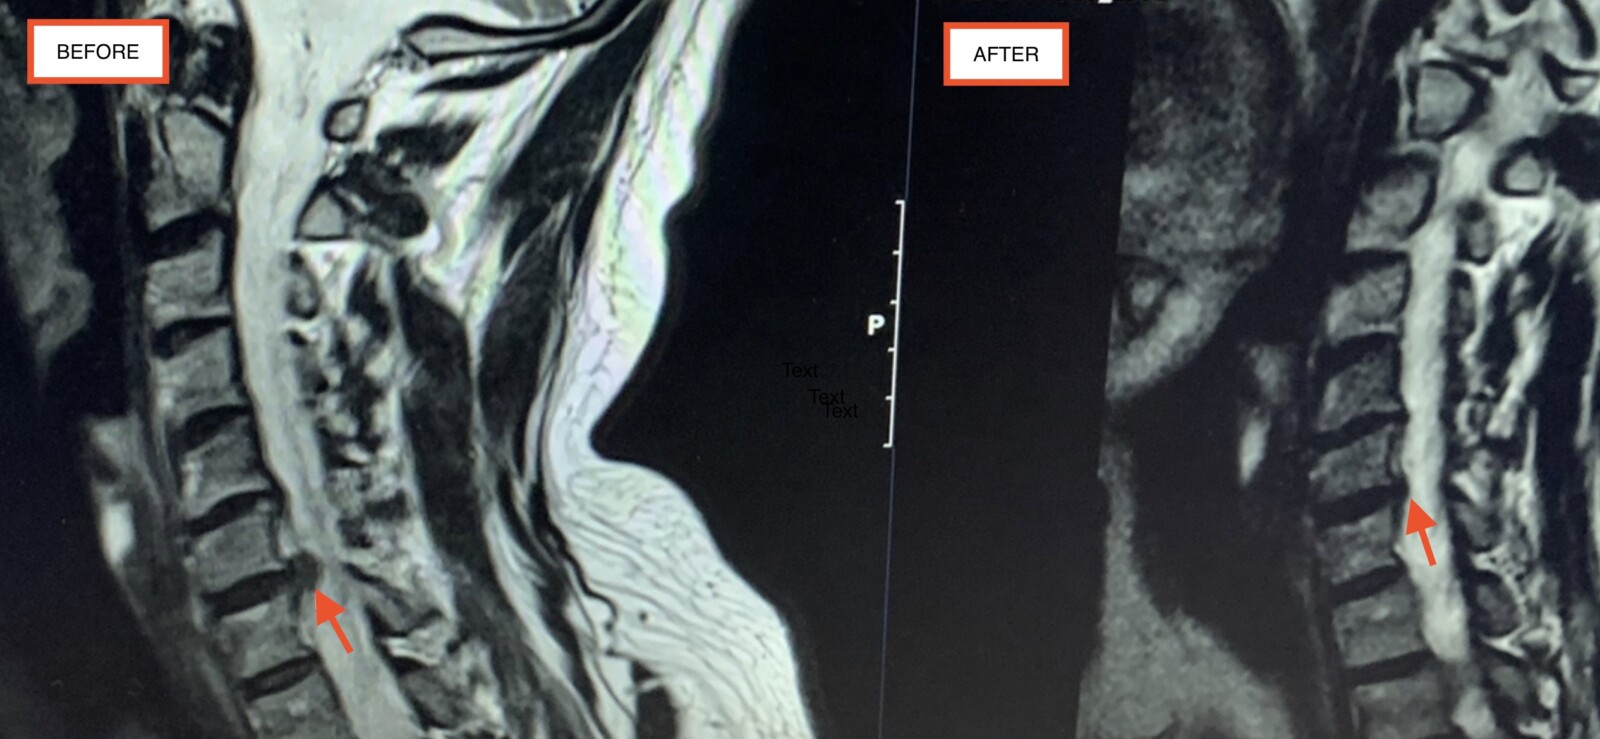

What Does A Herniated Disc Look Like On An XRay at Christopher Windham blog Can Golf Cause Herniated Disc Yes, you can play some sports with a herniated disc, but you may need to stop some high impact sports and activities for a time to let your spine recover. Depending on the severity, disc herniations can negatively affect the golf game due to the. I currently have l4 and l5 herniated and been through 2 streoid packs. Can i. Can Golf Cause Herniated Disc.